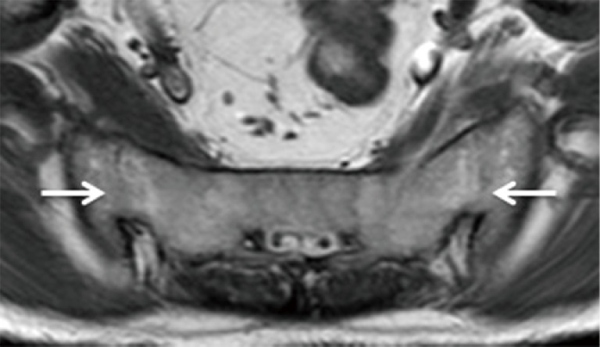

Hình ảnh CT viêm khớp cùng chậu

Hình ảnh chụp CT cho thấy gai xương xuất hiện ở rìa trước kèm tình trạng xơ cứng dưới sụn ở bên trái

Viêm khớp cùng chậu gây nhiễm trùng trên CT

Nghi ngờ viêm khớp cùng chậu nhiễm trùng, chọc kim vào khớp cùng chậu để hút dịch khớp.